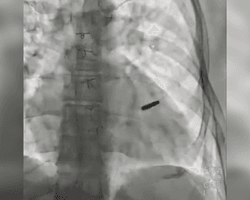

Воєнний фокус "Пощастило хлопцю": захисник "Азовсталі" провів три роки в полоні з кулею у серці (відео) 19.09.2025 12:59